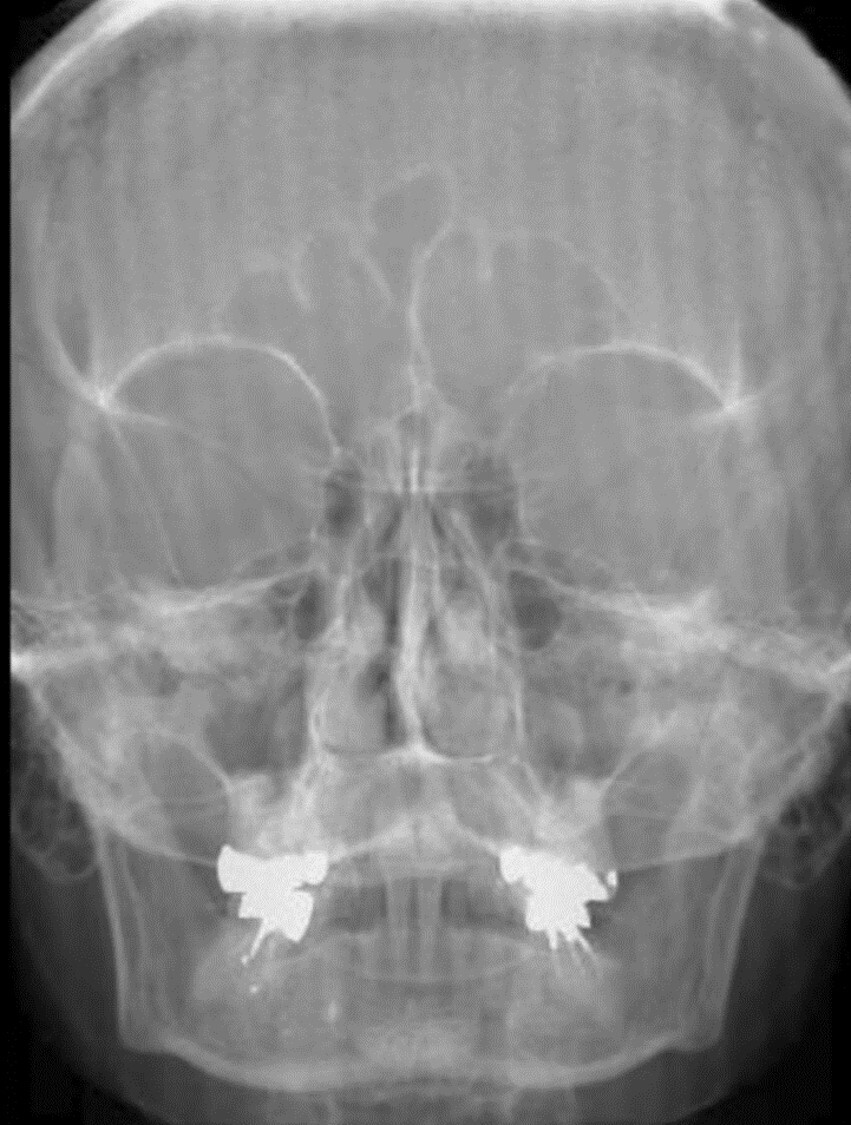

Q

Aside from the surgically implanted hardware, what artifact is seen in the attached image?

A

Quantum mottle from underexposure